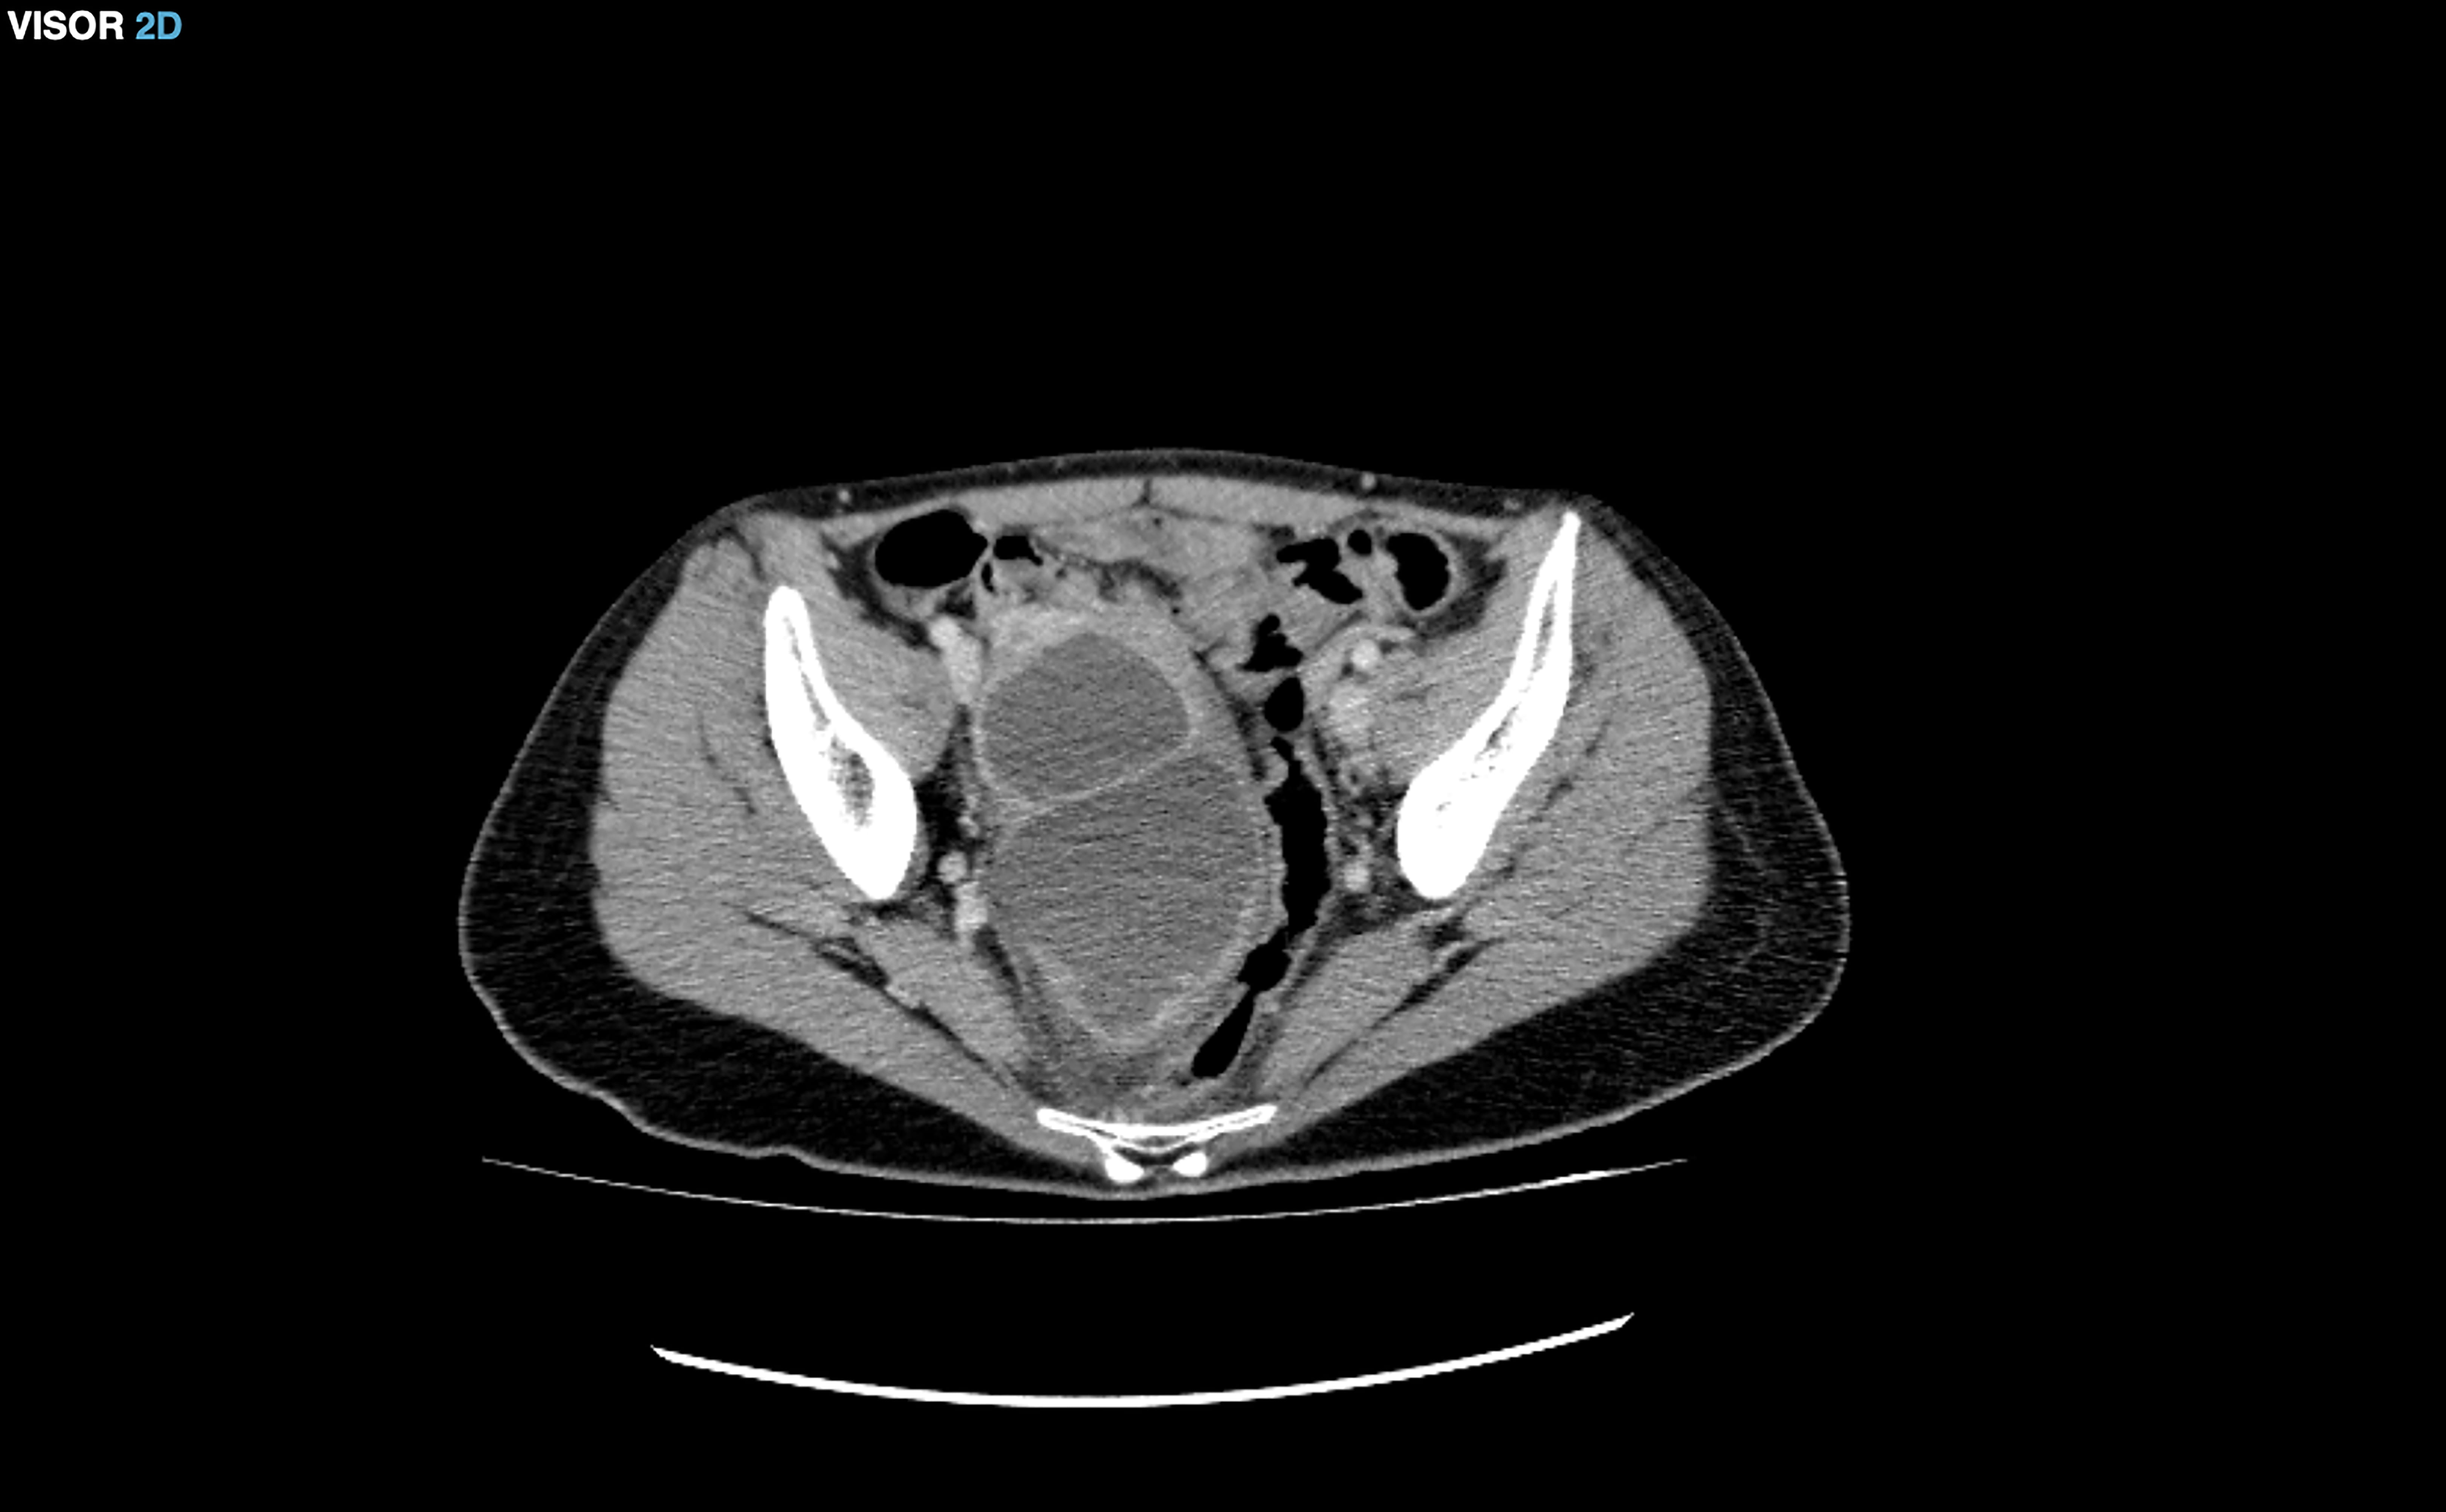

The patient came to the emergency department reporting intense abdominal pain and abdominal swelling for a month after having suffered a miscarriage at 6 weeks after a frozen embryo transfer performed at an external center. An emergency abdominal CT was performed, showing moderate ascites predominantly in the pelvic region (Fig. 2), which was initially treated with diuretics, albumin and anticoagulants.

Fig. 2.Moderate ascites in the pelvic region.